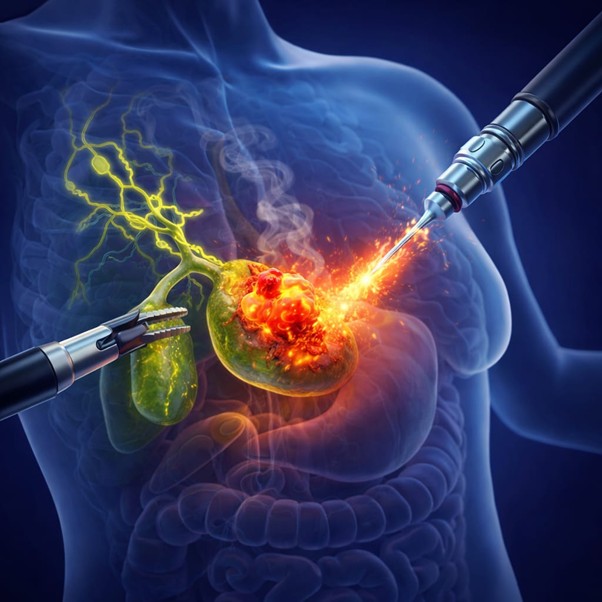

Gallbladder Tumor Treatment In Mira Road The Surprising Fact When it comes to Gallbladder Tumour Treatment in Mira Road, patients often face…

Introduction Gallbladder cancer surgery in Mira Road, let’s understand. Gallbladder cancer is a rare but aggressive disease that often requires timely surgical…